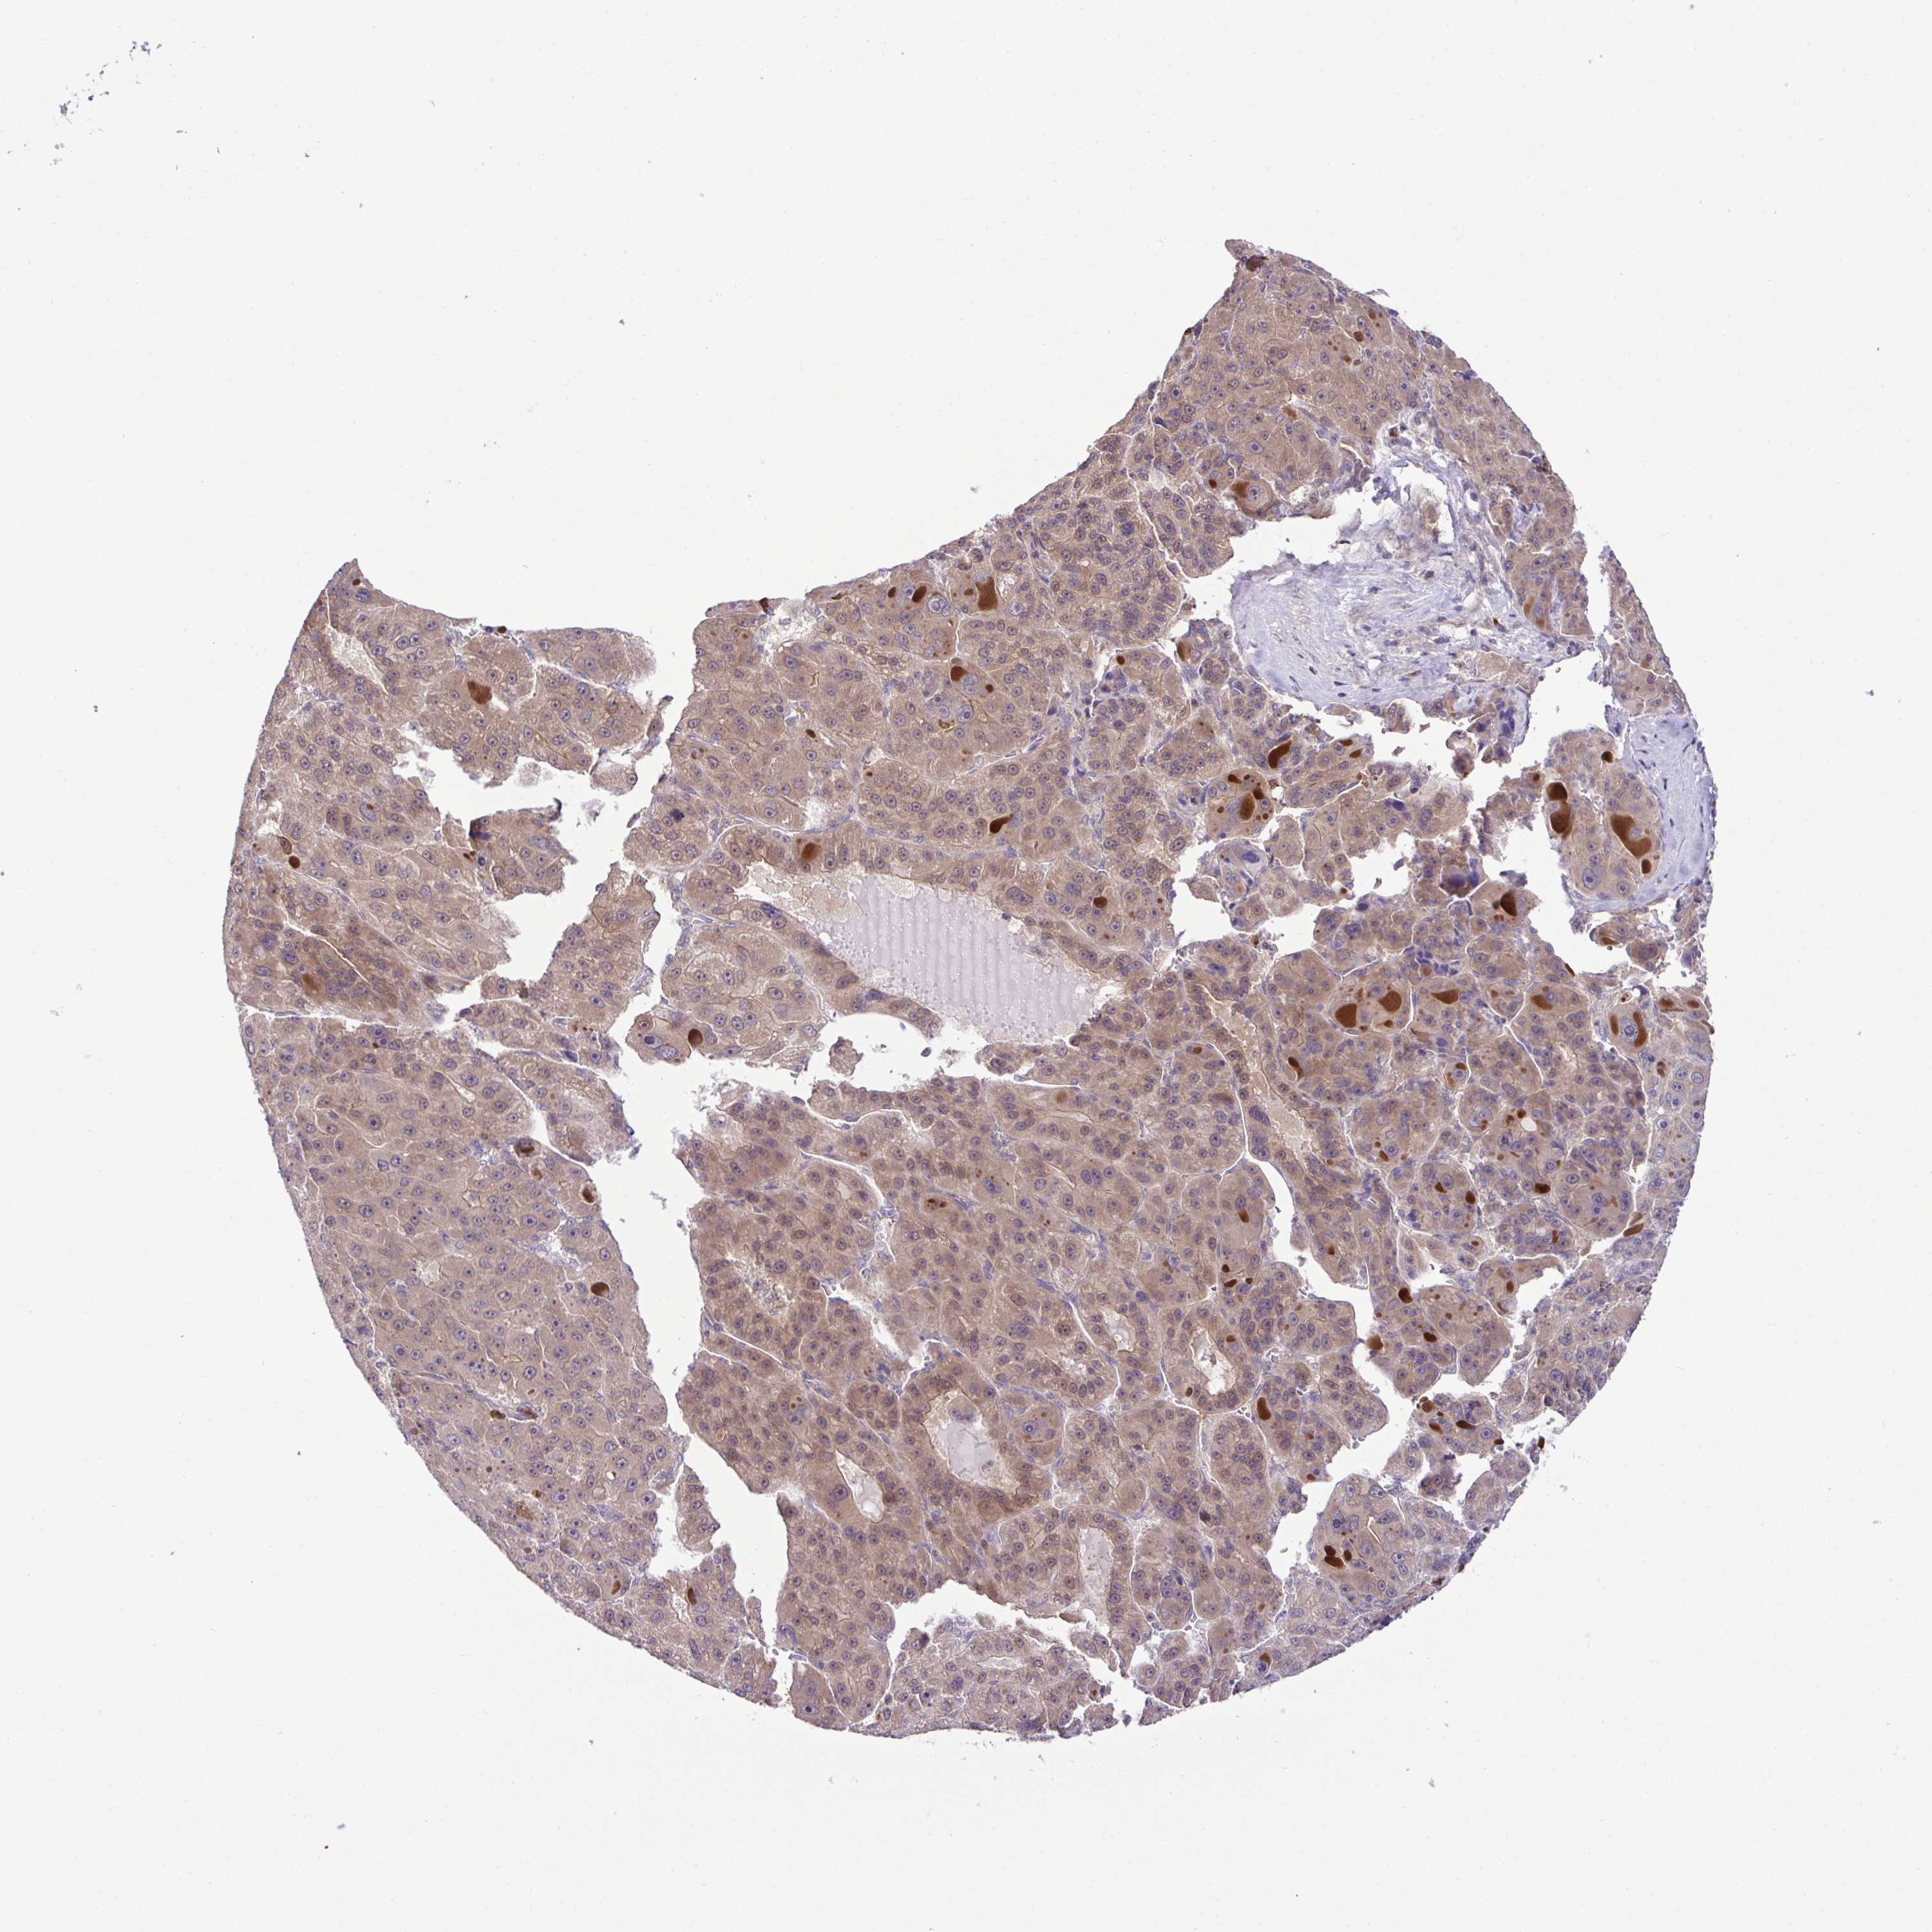

LIVER CANCER - Protein expressioni

A mouse-over function shows sample information and annotation data. Click on an image to view it in a full screen mode. Samples can be filtered based on level of antibody staining by selecting one or several of the following categories: high, medium, low and not detected. The assay and annotation is described here.

Antibody stainingi

Antibody staining in the annotated cell types in the current human tissue is reported as not detected, low, medium, or high, based on conventional immunohistochemistry profiling in selected tissues. This score is based on the combination of the staining intensity and fraction of stained cells.

Each image is clickable and will lead to virtual microscopy that enables deeper exploration of all samples and also displays staining intensity scores, fraction scores and subcellular localization as well as patient and tissue information for each sample.

Antibody HPA053730

Antibody HPA058604

Staining

High

Medium

Low

Not detected

Intensity

Strong

Moderate

Weak

Negative

Quantity

>75%

75%-25%

<25%

None

Location

Nuclear

Cytoplasmic/membranous

Cytoplasmic/membranous,nuclear

Cholangiocarcinoma

Carcinoma, Hepatocellular, NOS